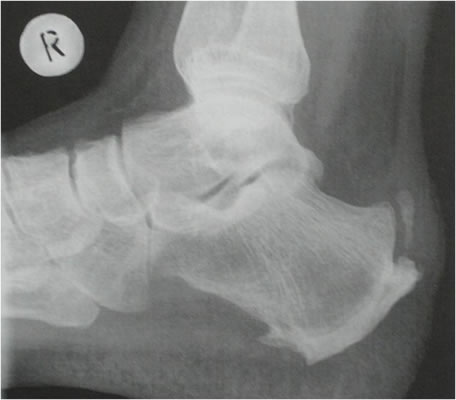

Fersensporn

Durch chronische Fehl- oder Überlastungen des Fußes kann es zu einer Reizung der flächenhaften Bindegewebsplatte der Fußsohle am knöchernen Ansatz des Fersenbeins kommen. Daraus resultiert häufig eine schmerzhafte Knochenhaut- und Sehnenentzündung. Der im Röntgenbild sichtbare Sporn zeigt die Chronizität und die Heilungsversuche des Körpers an und schmerzt selbst nicht. Bei Nichtbehandlung der Fersenschmerzen kann es zu Sehneneinrissen kommen, die einen langen Heilverlauf benötigen.